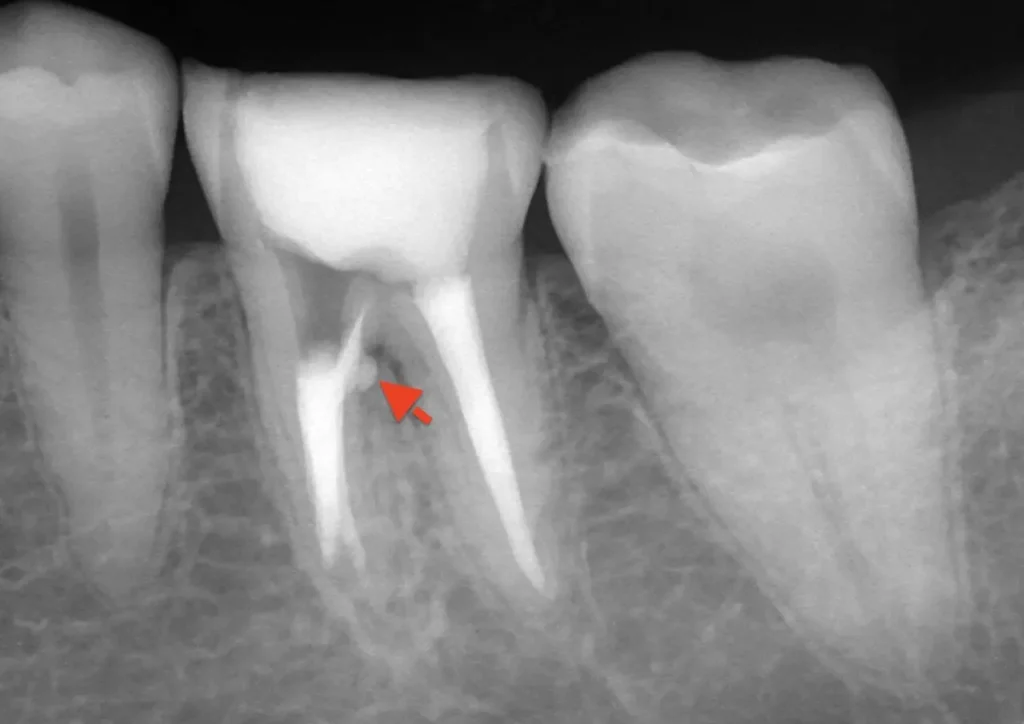

自費根管治療症例2 治療前

左下の奥歯が根の治療を受けているが治らない。

初診時

管の分かれている部分に根の治療による穿孔がありました

術中

穿孔部分の封鎖と通常の根管治療を行いました

術後

症状は、完全に消えて、穿孔部分の封鎖と確実な清掃、充填が確認できます

精密根管治療(自費根管治療)治療開始

精密根管治療(自費根管治療)、治療回数3回、治療期間約1ヶ月、治療費(大臼歯再治療)15万3千円+4,500円X3回  ジルコニアクラウン6万9千円

治療後

症状はすべて改善、経過2年後

症状もレントゲン上の炎症も全く再発はありません

治療は1回1時間程度で複数回。根の壁の封鎖材料は、MTAセメント。副作用もなく穿孔部分位の封鎖には最良な材料です。そのほか、バイオセラミック系の生体活性材料も現在は使用します。マイクロスコープを使用した精密根管治療では、ラバーダムシートの使用、無菌的操作が絶対条件です。